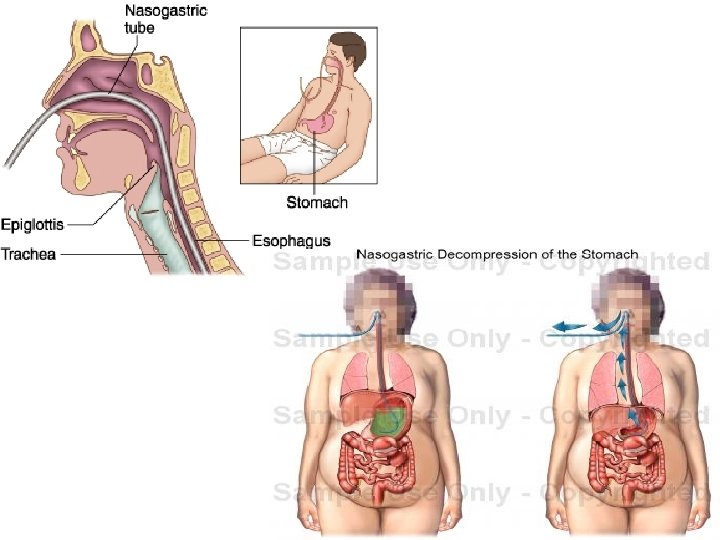

• TRAJTIMI DHE KUJDESI INFERMIEROR: - Pacienti me kolecistit akut duhet te hospitalizohet dhe te trajtohet si urgjence mjeksore. - Te percaktohet shpejt dhe sakte diagnoza. - Nderpritet kategorikisht ushqimi nga goja. - Vendoset sonda NG per te bere evakuimin e lengjeve gastrike e duodenale per te qetesuar keshtu te vjellat dhe dhimbjen abdominale e duke menjanuar kontraksionet e kolecistes.

TRAJTIMI DHE KUJDESI INFERMIEROR - Regjistrimi dhe vlersimi I ankesave te pacientit Hospitalizimi STOP ORAL Rehidratimi me glukoze, fiziologjike me doza te larta - Aspirimi I lengjeve duodenale dhe intestinale me sonde NG dhe tub aspirimi - Nderhyrje kirugjikale urgjente - Trajtohet gjendja e shokut